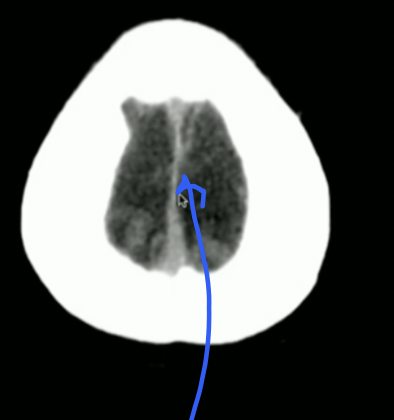

<p>Is this normal/abnormal?</p>

Is this normal/abnormal?

• Normal: the Choroid Plexus can Naturally Calcify